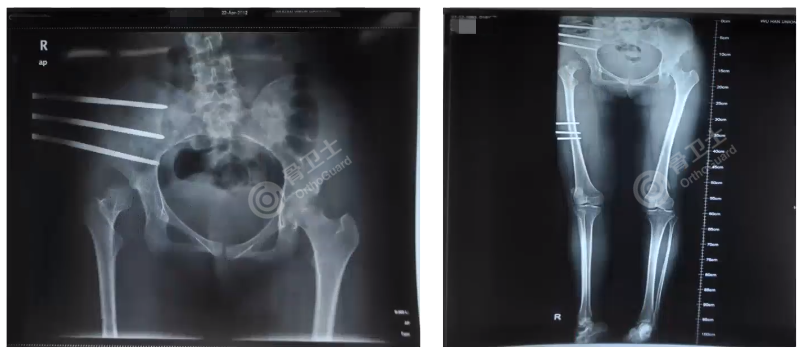

对于业内存在的年轻人不建议做全髋关节置换的观点,杨述华教授则认为,患者骨骼发育成熟之后就可以做髋关节置换,早期采用关节置换,可以将肌肉力量调整到正常水平,效果是非常好的。杨述华教授介绍了股骨转子下缩短截骨全髋关节置换的好处,包括髋关节活动度良好,Harris评分显著改善,肢体不平衡显著改善,影像学结果满意,可以防止坐骨神经麻痹性损伤。截骨的方法包括横形截骨,斜形截骨,梯形截骨,V型截骨,临床中横形截骨使用较多,梯形截骨稳定性较好。对于如何确定截骨线,杨述华教授指出,近段截骨线一般以小转子下面作为基准,截多少,需要把假体放进髋臼中看重叠多少,重叠的部分就是需要截掉的部分,还需要和对侧长短做对比,需要与对侧等长。

关于全髋关节置换术的并发症,杨述华教授指出,全髋关节置换术的并发症相对较多,常见的并发症包括术中骨折、坐骨神经损伤、髋关节脱位、截骨端延迟愈合或不愈合、无菌性松动、翻修等。最后,杨述华教授详细介绍了武汉协和医院独创的“外固定器牵引+全髋关节置换术”,不截骨就可以解决年轻人高位脱位型髋关节发育不良。此类患者一般双下肢不等长较为严重,为了平衡患者肌肉力量,手术前,在患侧做骨外牵引,将一侧钉子打在髋臼上面,另外一侧打在股骨干上面,每天牵引延长1-2mm,经过2周左右时间,可发现股骨头可牵引至真臼,再做关节置换。术后用外固定延长器延长,每天延长3-5mm,平衡肌力,达到纠正肢体短缩的目的,避免转子下做截骨,同时对于改善骨盆缺血、骨盆倾斜效果明显。